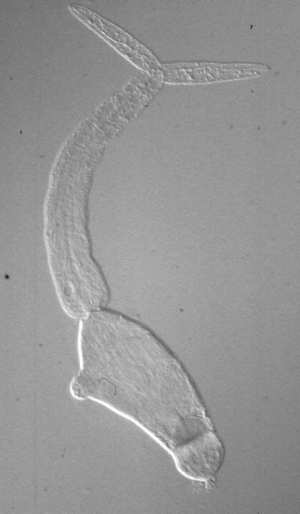

Schistosoma mansoni cercariae

S. mansoni cercariae, © T. Loy